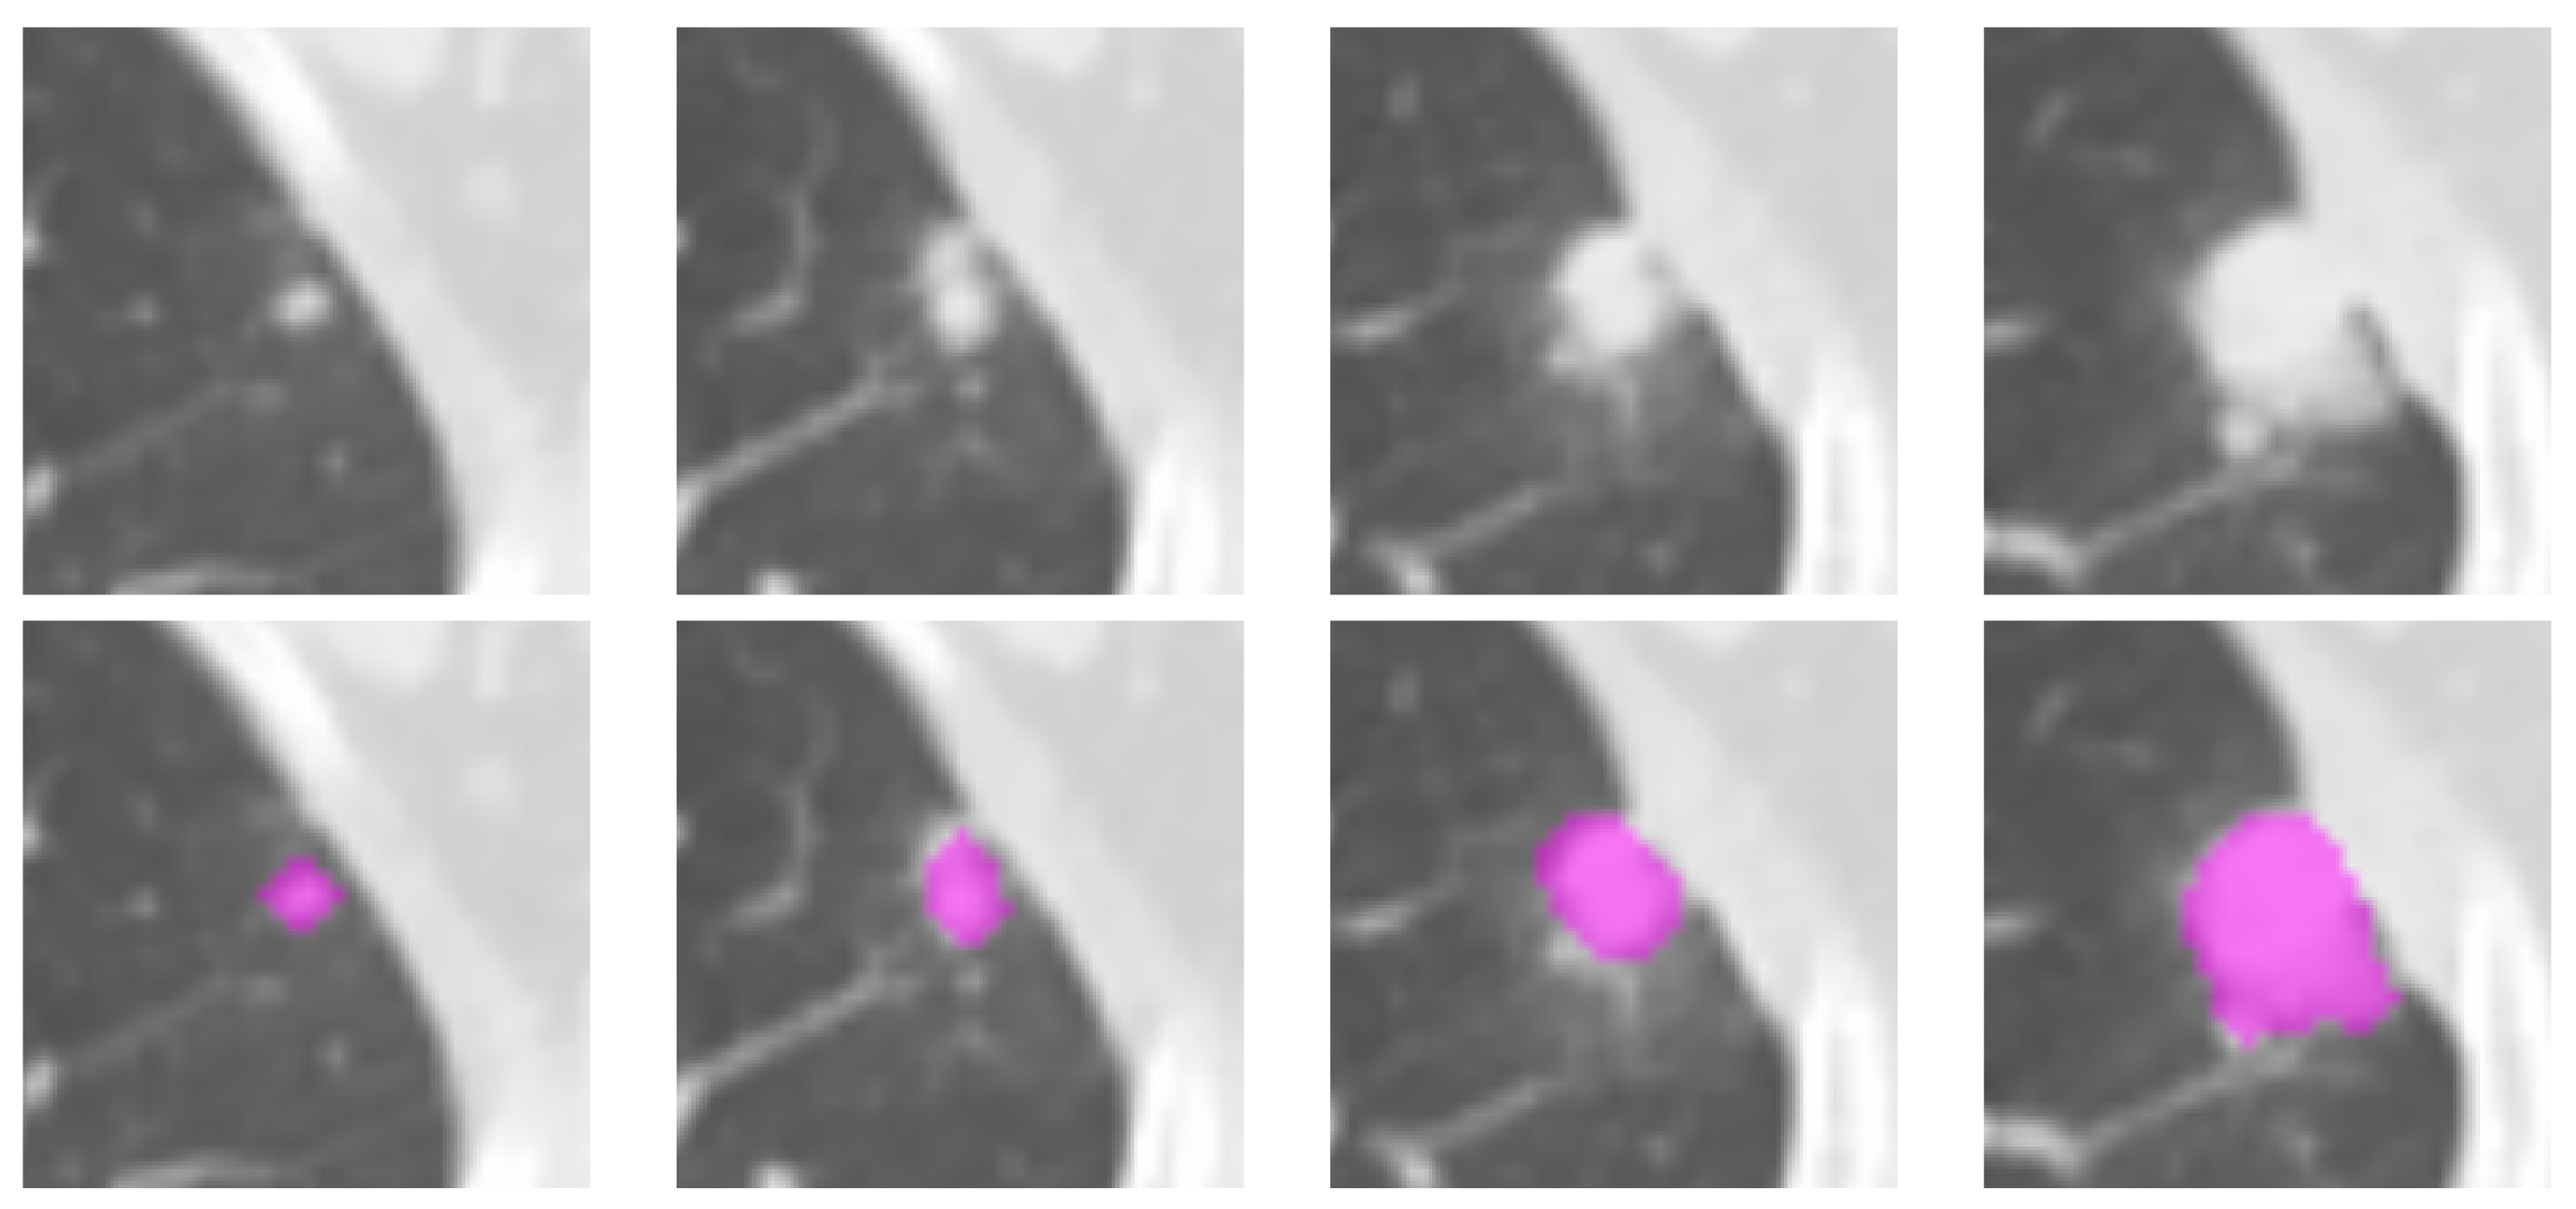

2.2. Lesion Delineation